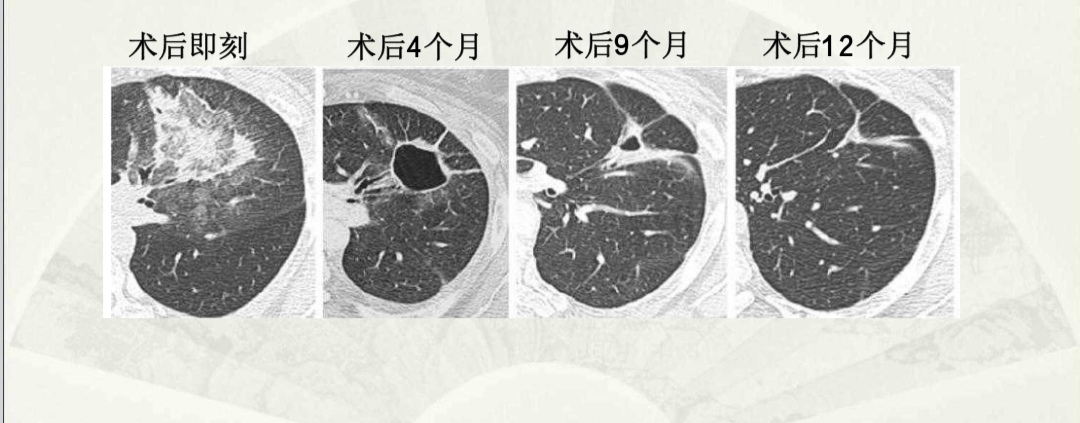

采用微波消融治疗肺癌有哪些优势?

1、微创:治疗中只用直径2mm左右的穿刺针在影像设备引导下精确进入肿瘤内,皮肤只有米粒大小的针眼,无疤痕,无缝线,避免了大手术对全身 “元气”的伤害,病人恢复快。

2、 治疗时间短,疗效确切:单发病灶≤5cm的肿瘤可一次灭活,一次治疗时间只需约10~15分钟。

3、可以进行适形消融:就是依据肿瘤的形状进行系统治疗,确保疗效,减少复发。

4. 适应证广:对于无法采用手术切除的,仍能进行微波消融治疗,尤其针对于老年患者和肺功能差的患者;可以达到缩减肿瘤、减缓疼痛、延长生命、提高生活质量等作用;对于术后复发和

转移性病灶,亦有很好的疗效。

5、可以有效联合其他治疗:病人采用微波微创消融治疗肺癌,损伤小,康复快,不伤元气,可以高效的联合放疗、 化疗、靶向药物、栓塞等,联合效果更优